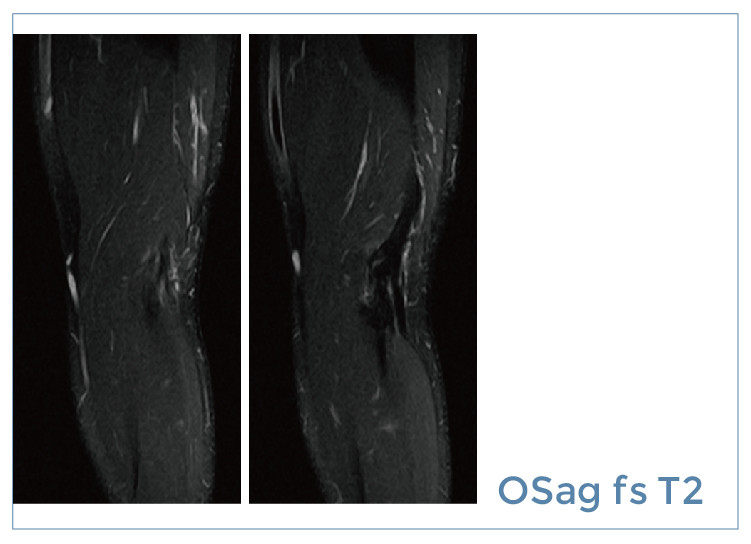

【朗润影像档案】20190726磁共振影像病例结果讨论